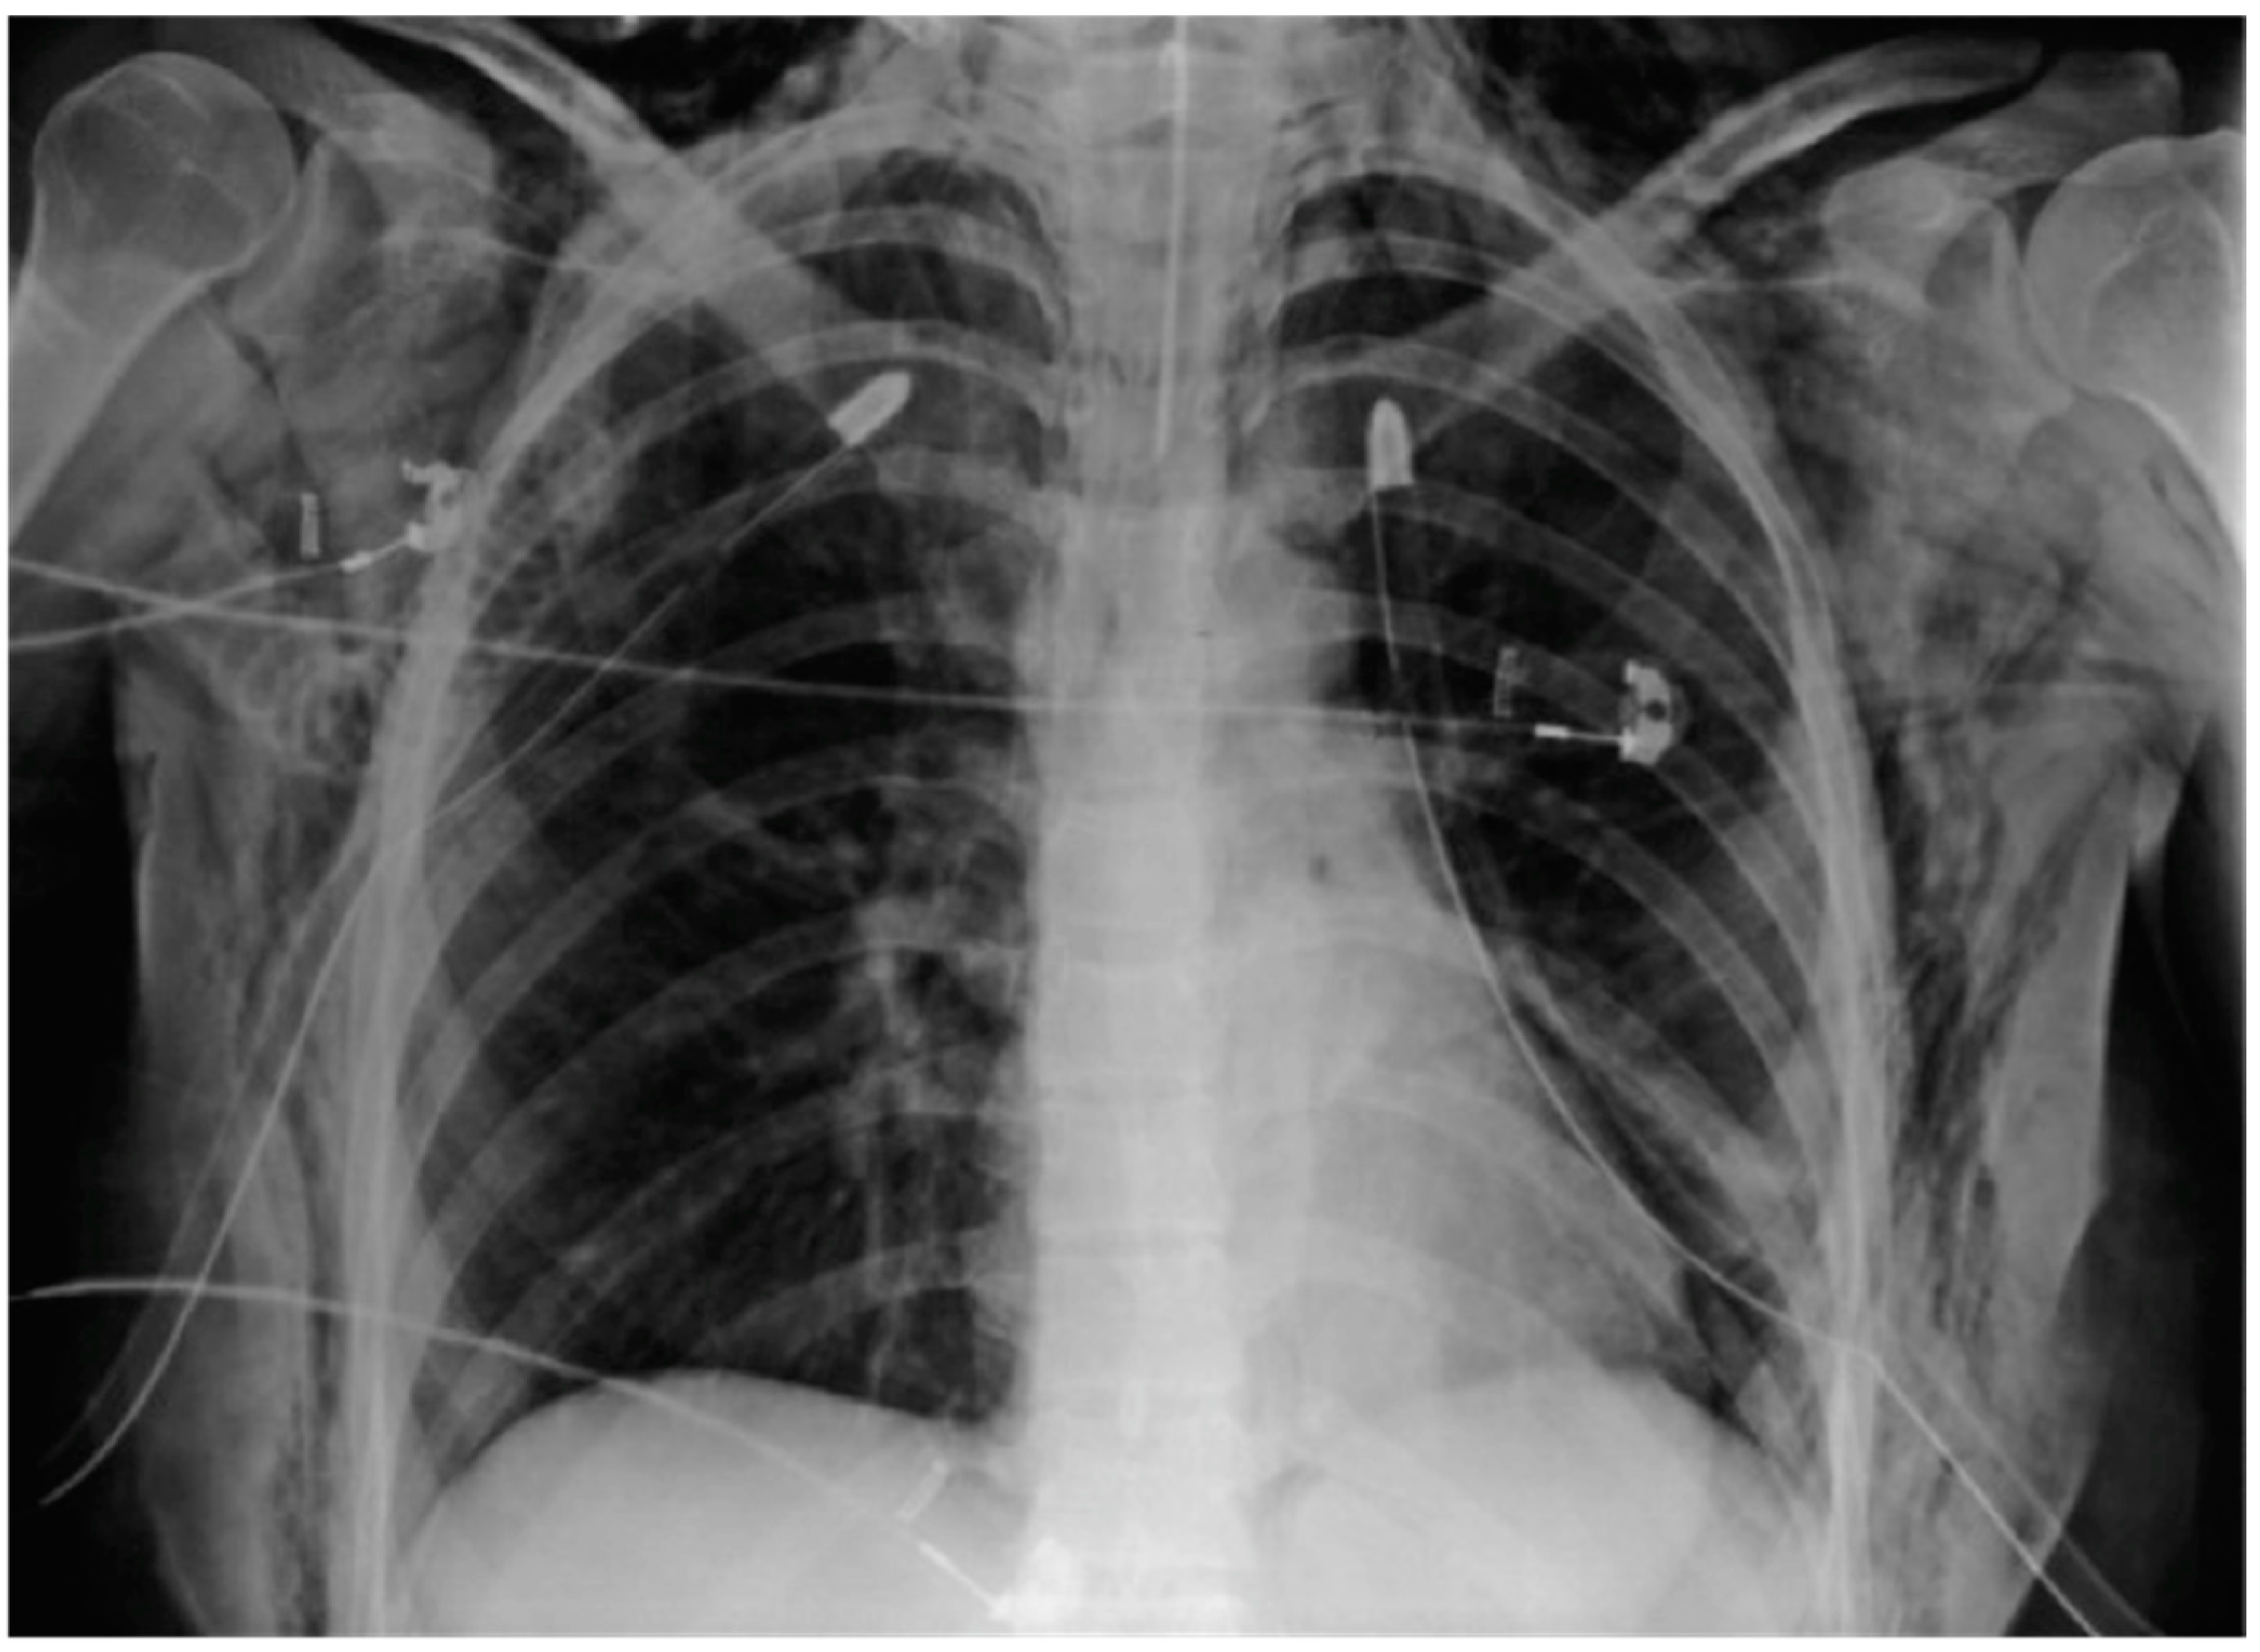

| Bilateral Pneumothorax | 1 | 1.72 |